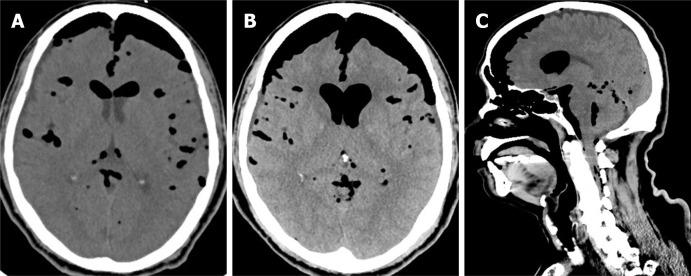

A 66-year-old man who received thoracoscopic resection to remove an intrathoracic, posterior mediastinal, dumbbell-shaped, pathology-proven neurogenic tumor. The patient then reported experiencing progressively severe headaches, especially when in an upright position. A brain computed tomography scan at a local hospital disclosed extensive pneumocephalus. Revision surgery for resection of the pseudomeningocele and repair of the cerebrospinal fluid leakage was thus arranged for the patient. During the operation, we traced the cerebrospinal fluid leakage and found that it might have derived from incomplete endoscopic clipping around the tumor stump near the dural sac at the T3 level. After that, we wrapped and sealed all the possible origins of the leakage with autologous fat, tissue glue, gelfoam, and duraseal layer by layer. The patient recovered well, and the computed tomography images showed resolution of the pneumocephalus.

一名66岁男性接受胸腔镜切除术以切除一枚位于胸腔内、后纵隔的哑铃形、病理证实的神经源性肿瘤。患者随后报告头痛逐渐加重,尤其是在直立位时。当地医院的脑部计算机断层扫描显示广泛气颅。因此为患者安排了修复假性脑膜膨出和修复脑脊液漏的翻修手术。手术中,我们追踪脑脊液漏,发现其可能源于T3水平硬脊膜囊附近肿瘤残端周围内镜夹闭不完全。之后,我们用自体脂肪、组织胶、明胶海绵和硬脑膜封闭剂逐层包裹并密封所有可能的漏出部位。患者恢复良好,计算机断层扫描图像显示气颅消失。